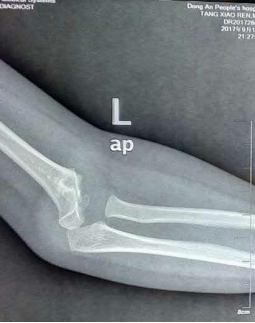

術后復查X片:提示骨折對位對線解剖復位,克氏針置入位置良好